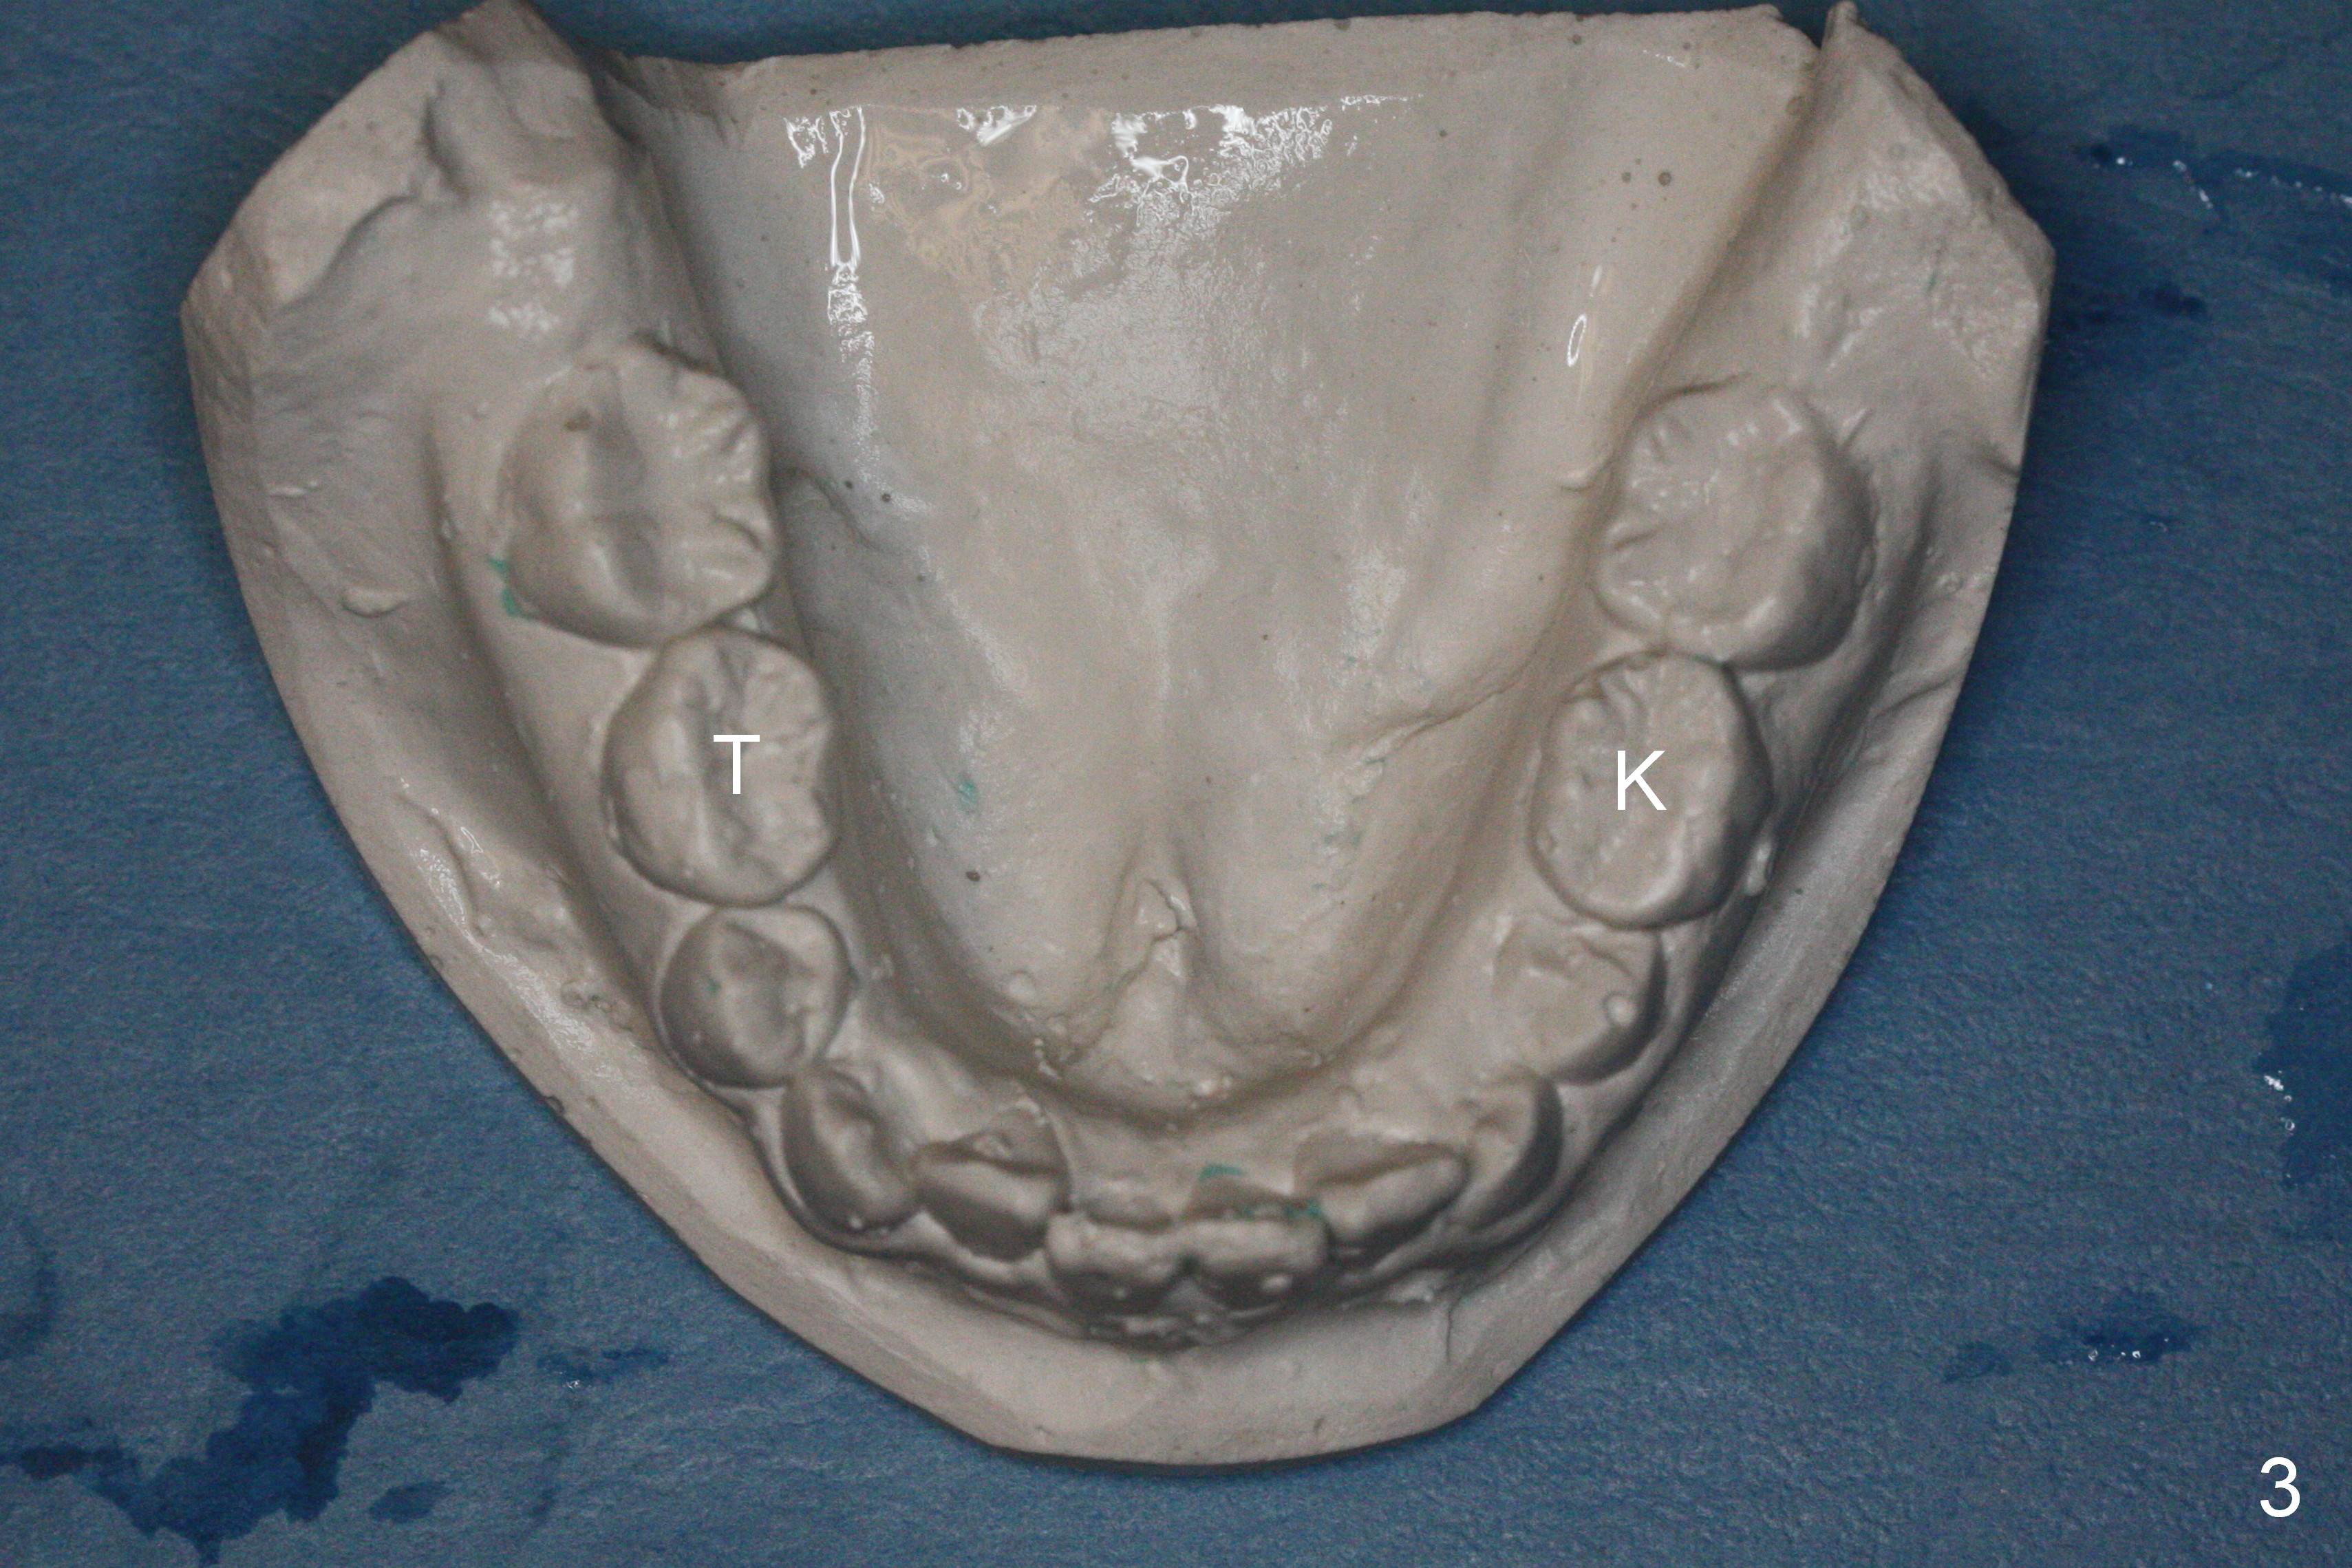

Panoramic X-ray shows underdevelopment of #20 and 29 tooth buds (Fig.6), which is related to K and T being retained (Fig.3). What should be done for K and T as well as 20 and 29?